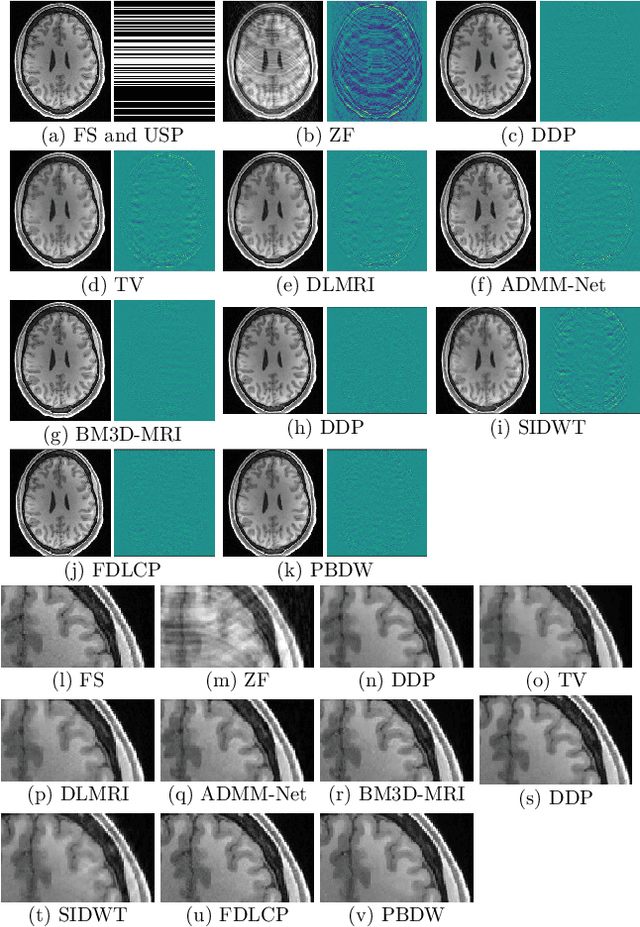

Purpose: MR image reconstruction exploits regularization to compensate for missing k-space data. In this work, we propose to learn the probability distribution of MR image patches with neural networks and use this distribution as prior information constraining images during reconstruction, effectively employing it as regularization. Methods: We use variational autoencoders (VAE) to learn the distribution of MR image patches, which models the high-dimensional distribution by a latent parameter model of lower dimensions in a non-linear fashion. The proposed algorithm uses the learned prior in a Maximum-A-Posteriori estimation formulation. We evaluate the proposed reconstruction method with T1 weighted images and also apply our method on images with white matter lesions. Results: Visual evaluation of the samples showed that the VAE algorithm can approximate the distribution of MR patches well. The proposed reconstruction algorithm using the VAE prior produced high quality reconstructions. The algorithm achieved normalized RMSE, CNR and CN values of 2.77\%, 0.43, 0.11; 4.29\%, 0.43, 0.11, 6.36\%, 0.47, 0.11 and 10.00\%, 0.42, 0.10 for undersampling ratios of 2, 3, 4 and 5, respectively, where it outperformed most of the alternative methods. In the experiments on images with white matter lesions, the method faithfully reconstructed the lesions. Conclusion: We introduced a novel method for MR reconstruction, which takes a new perspective on regularization by using priors learned by neural networks. Results suggest the method compares favorably against the other evaluated methods and can reconstruct lesions as well. Keywords: Reconstruction, MRI, prior probability, MAP estimation, machine learning, variational inference, deep learning